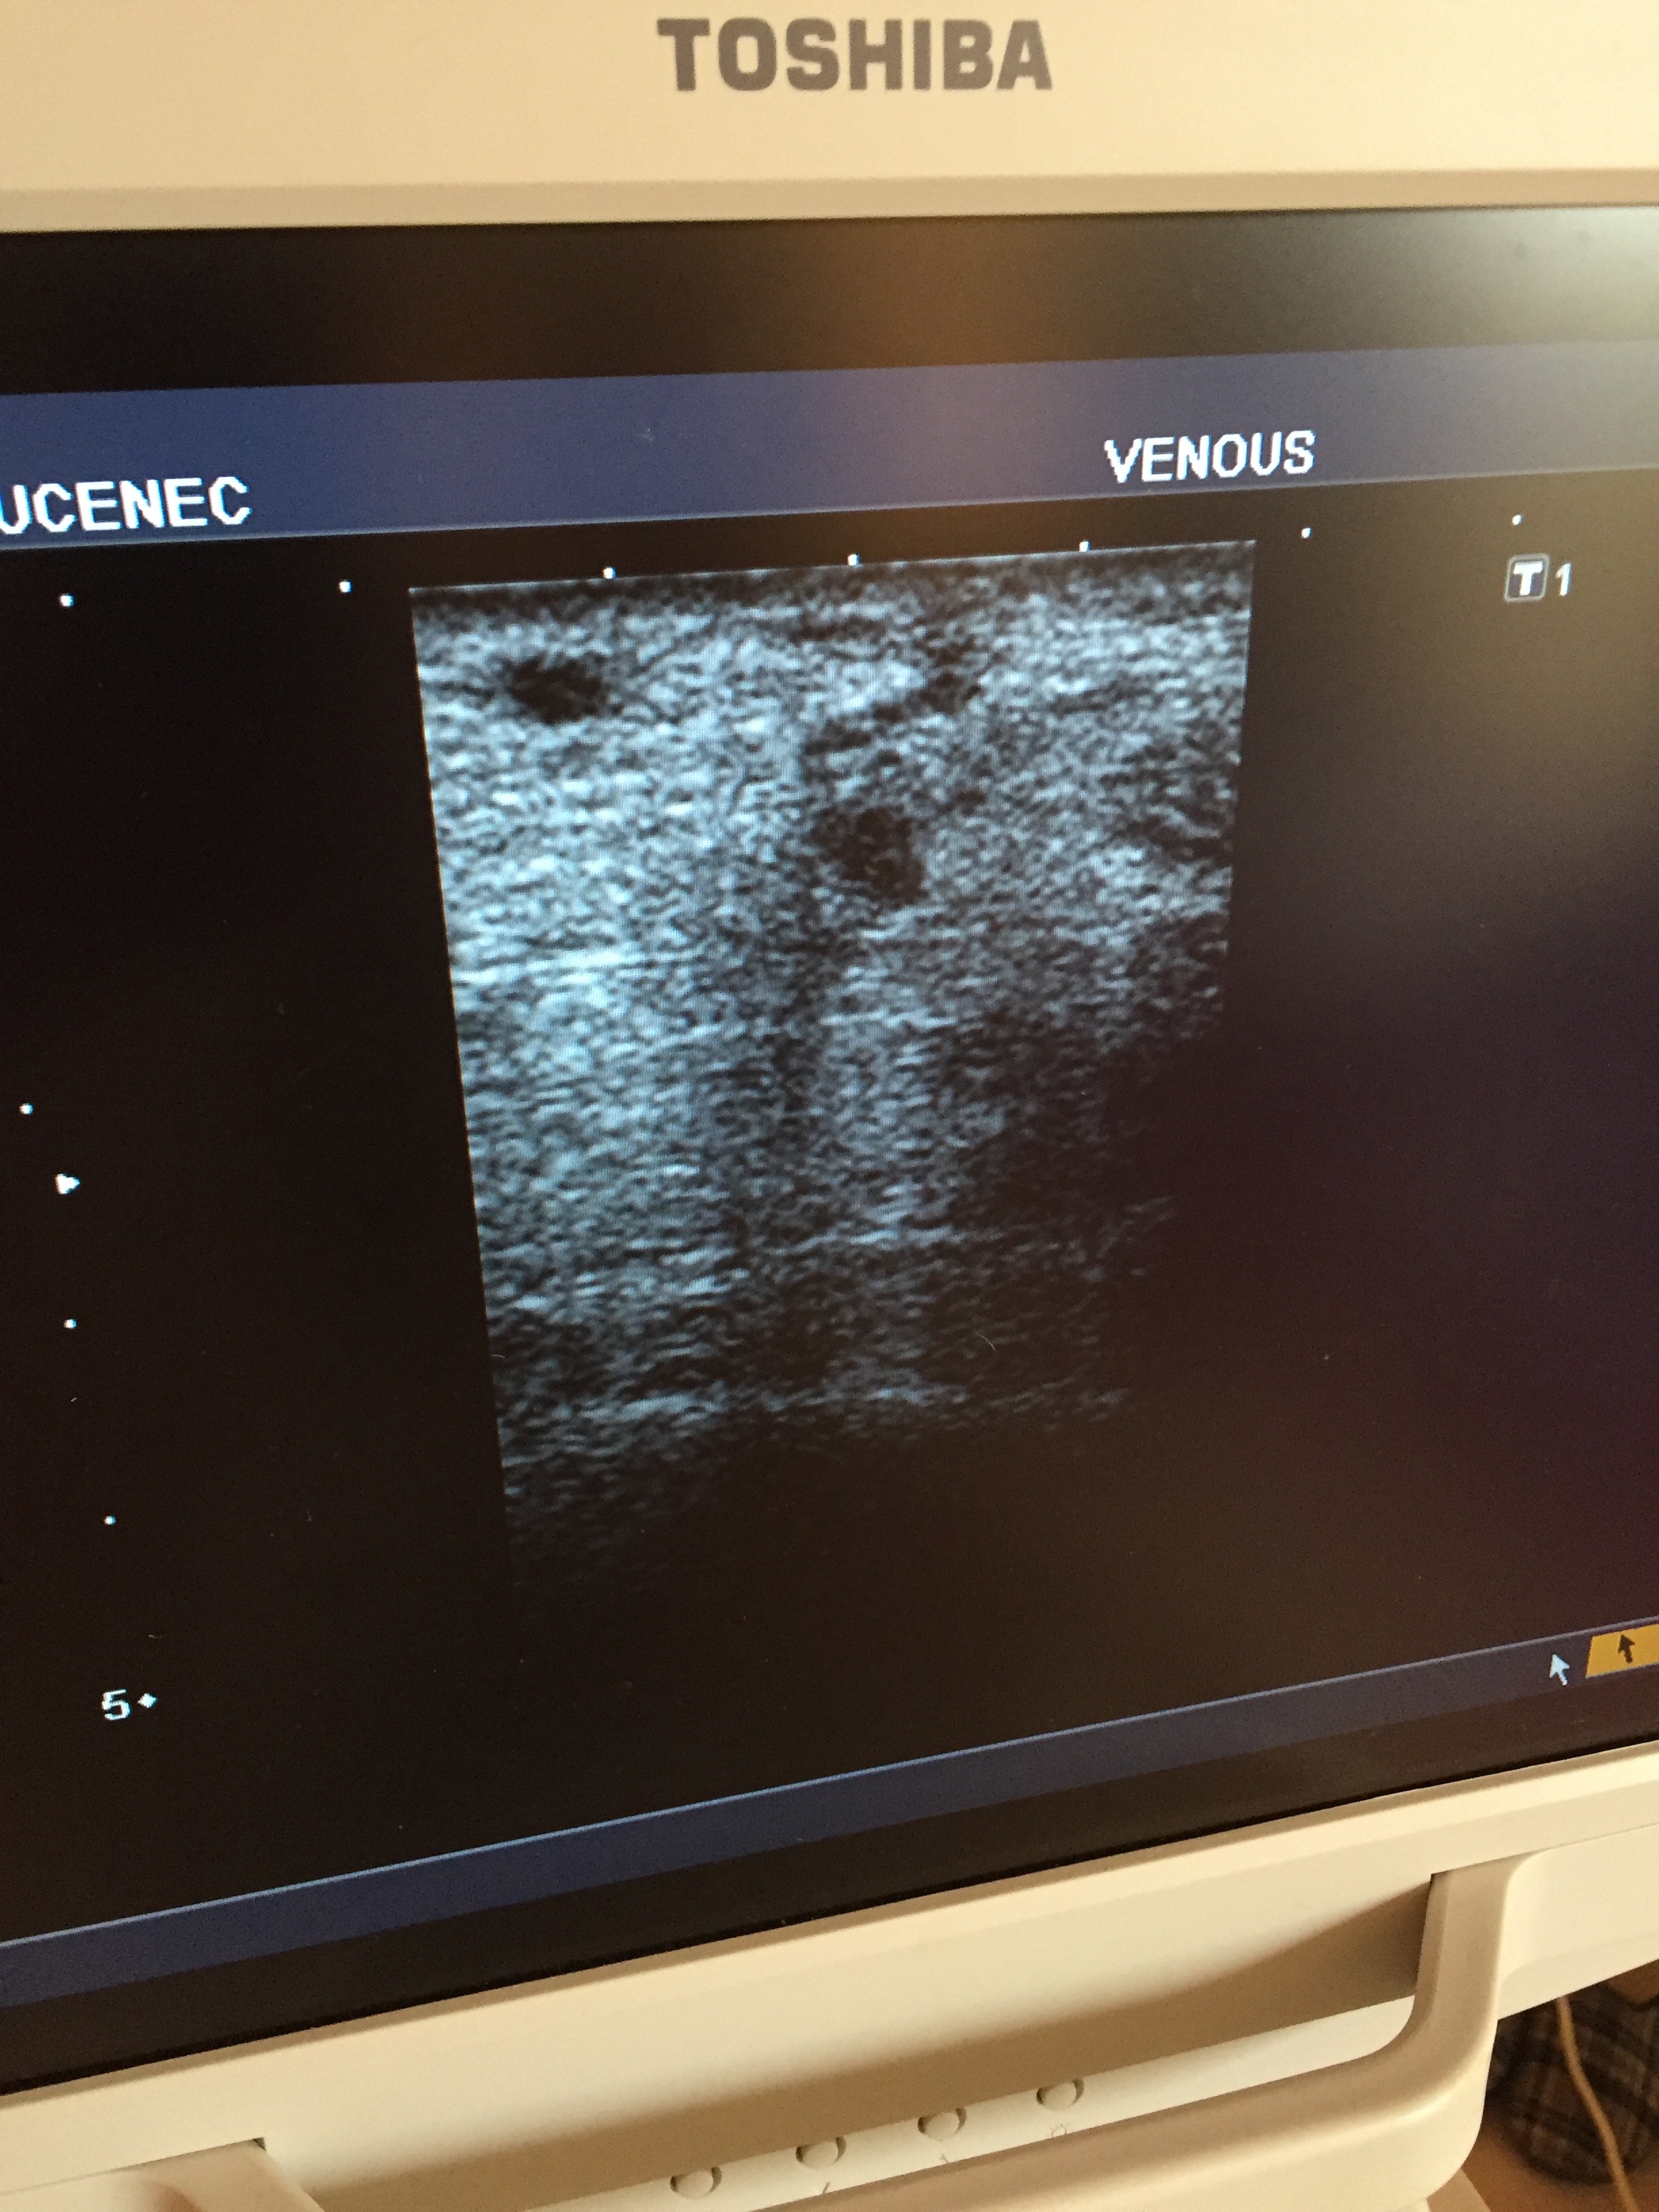

Sklerotizácia pod sonografom

Žena, 60 rokov